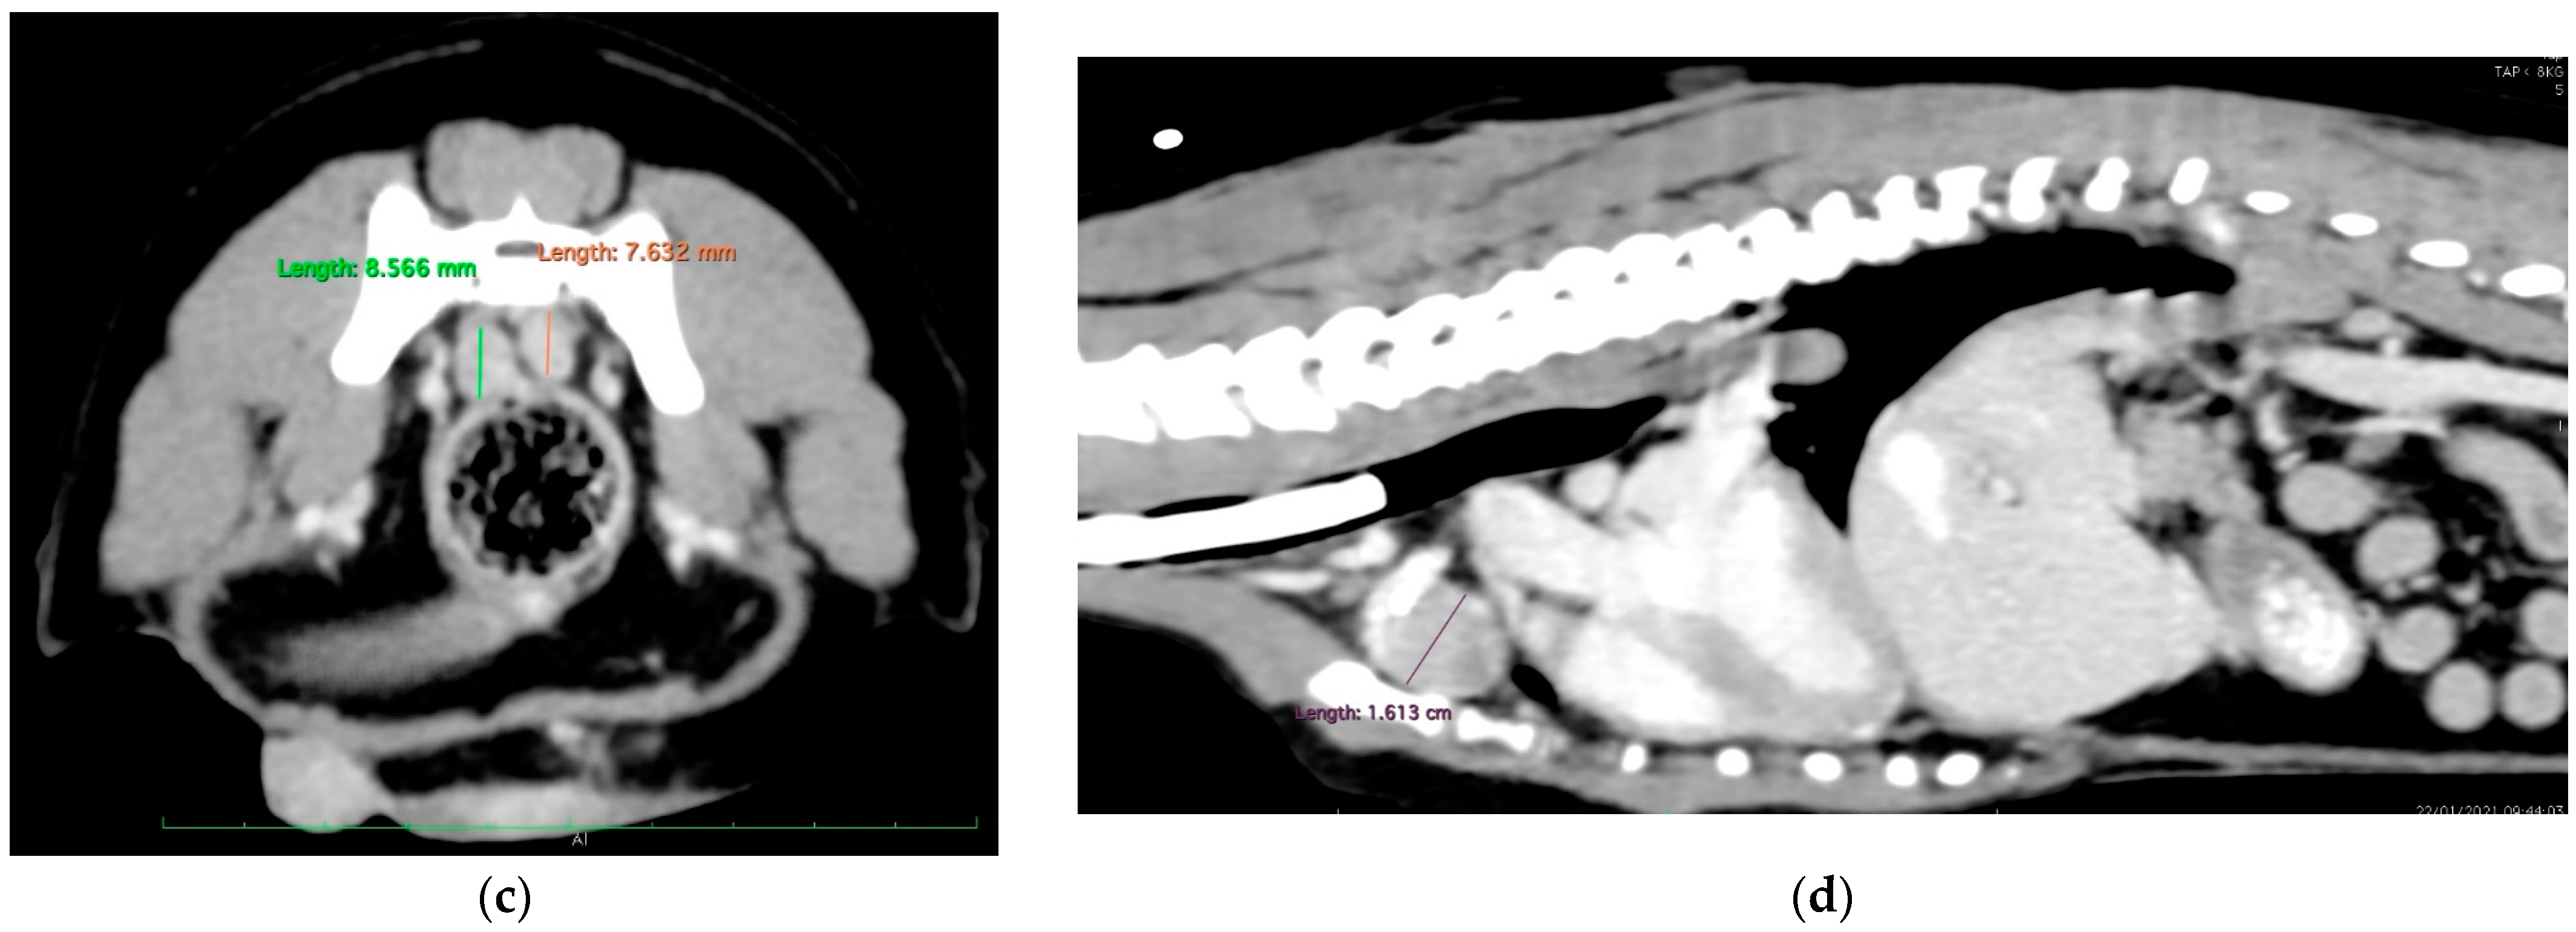

Five weeks after the last carboplatin chemotherapy treatment, firocoxib and toceranib were reinstated despite persistent thrombocytopenia. The presence of a flaccid tail was noted 7 days later, followed by the acute development of posterior paresis within 24 h. A CT examination (Figure 6) revealed several spinal metastases but no other locations of metastases, and the dog died on the next day. In order to respect the owners’ wishes, necropsy was not performed. The time from initial surgery (carried out in our referral center) to death from the mammary tumor was 218 days (7 months and 6 days).

Figure 6.

The CT scan examination at the end. The C6, L3, L6, L7, S1 and S2 vertebral bodies showed cookie-cutter lesions, pointed by the arrows. (The lesion at L6 severely invaded the medullary canal; not shown here).